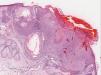

In the pathology study, a well-defined neoplastic proliferation was observed in the superficial dermis in contact with the epidermis. It was made up of squamous cells, some with vacuolization, with foci of keratinization and microcysts. Focal erosion of the surface was present, with a serohematic crust. In addition, the dermis showed a reactive lymphohistiocytic infiltrate with vascular dilation that also involved the periphery of the lesion (Fig. 2). Diagnosis of trichilemmoma was established.

Histological image (hematoxylin and eosin, x8). A well-defined neoplastic proliferation was observed in the superficial dermis, in contact with the epidermis. It was made up of squamous cells, some with vacuolization, with foci of keratinization and corneal microcysts. Note the ulcerated epidermis and dilated vessels in the tumor periphery (arrows).